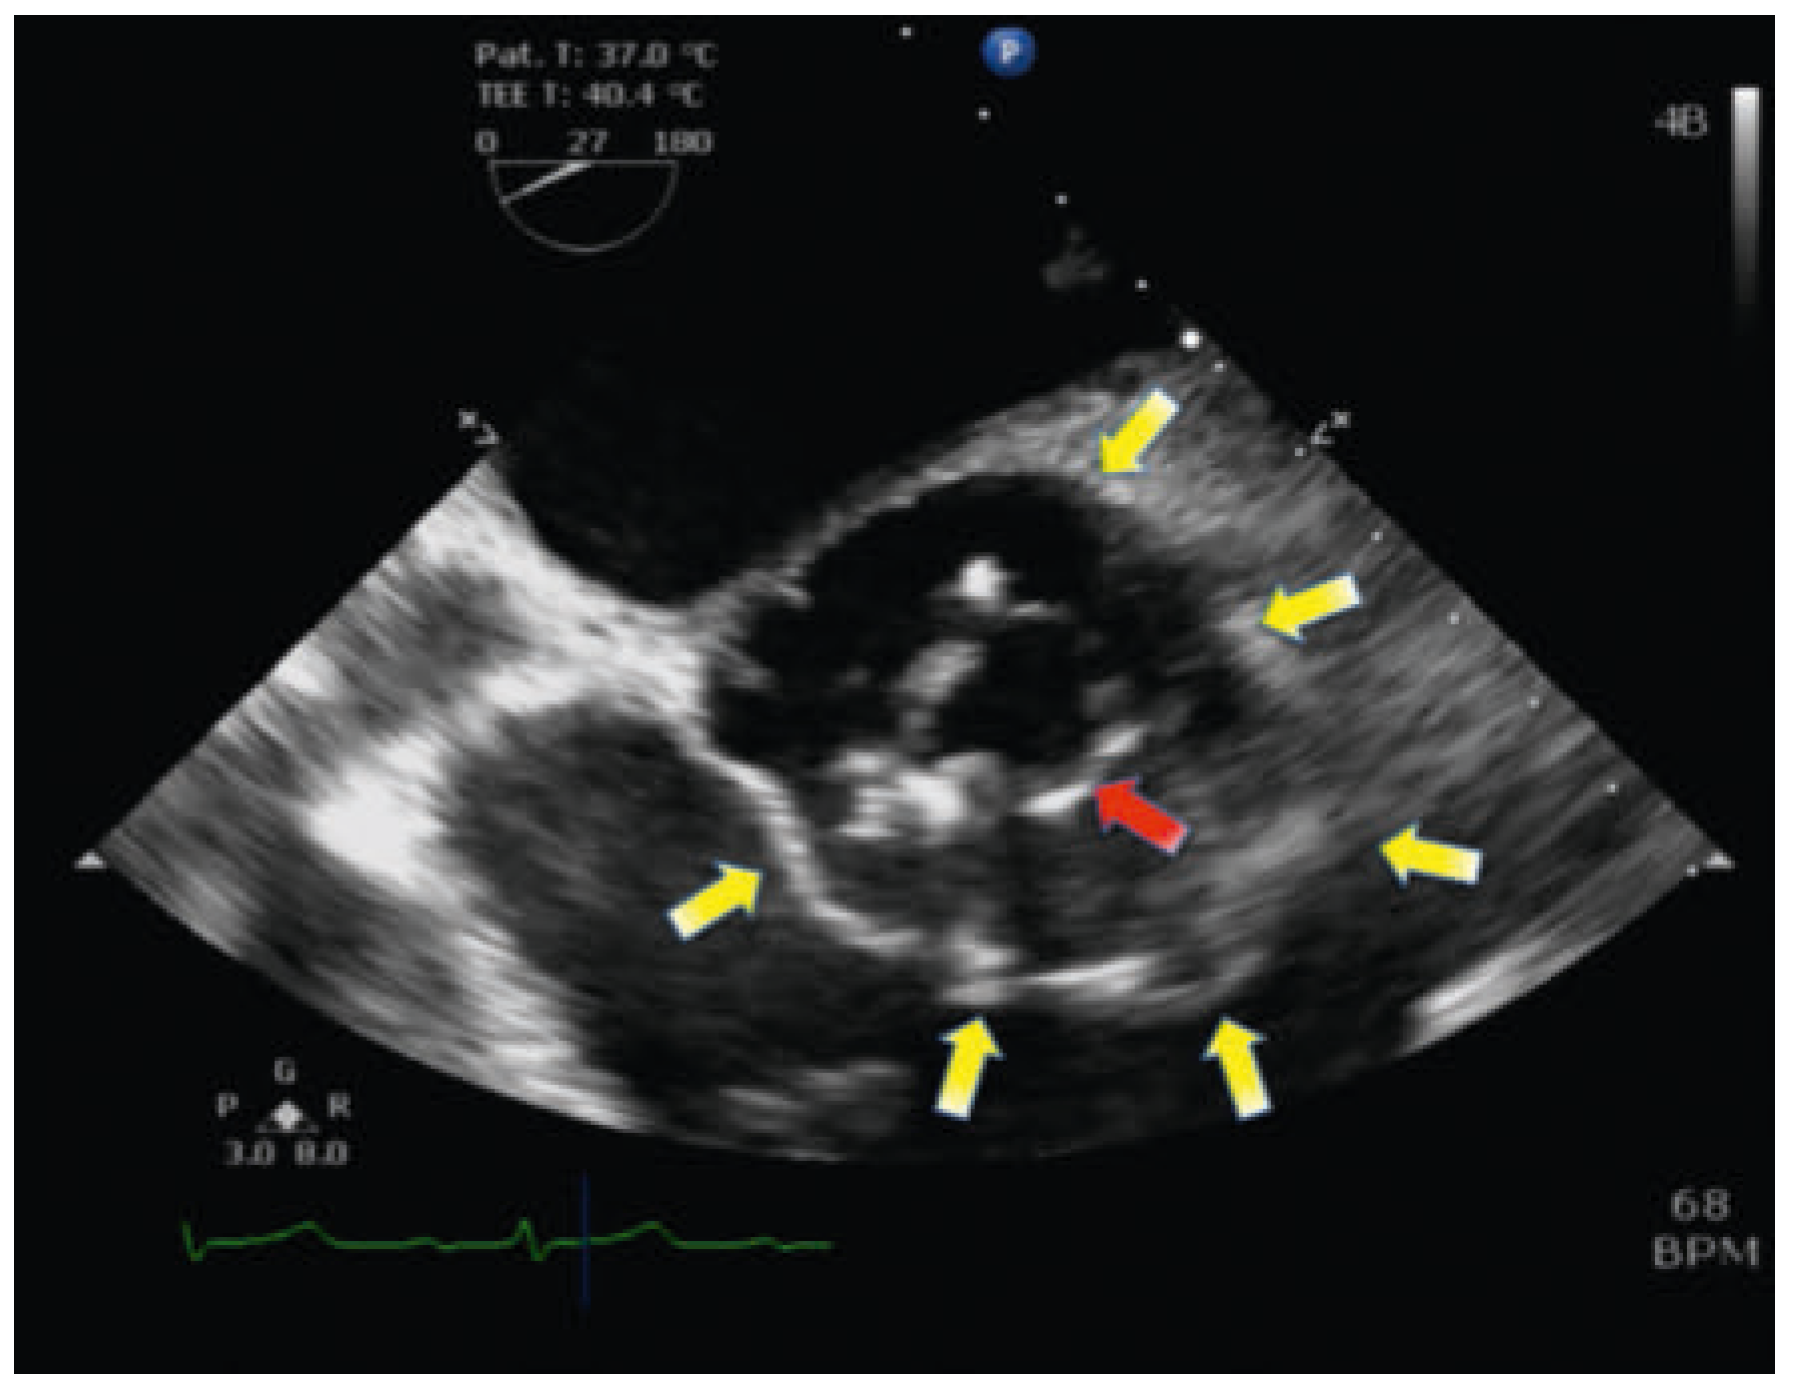

In this case the involvement of an endocarditis team was necessary to coordinate the following therapy. One week after adjustment of the antibiotics to penicillin, according to sensitivity analysis of the bacterium, the knee endoprosthesis was explanted in total. During the operation we performed a TOE, which showed an increase in the vegetation length to 1.6 cm. The following day preoperative diagnostic tests including computed tomography for exclusion of septic embolism and coronary angiography were performed (Figure 2). The patient was scheduled for cardiac operation 3 days after explantation of the knee prosthesis. Surprisingly, concerning cardiac complaints, the patient remained oligosymptomatic.

Figure 2. Coronary angiography: Contrast medium shows an enlargement of the aortic root without insufficiency.